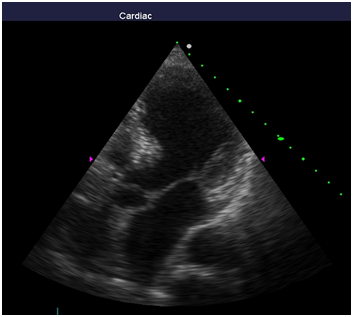

Repeated echocardiography revealed the zone of violation of local contractility (akinesis and pronounced hypokinesis) all segments on the medial and apical level with the formation of acute left ventricular aneurysm, a marked reduction of EF (23%), hyperkinesis all segments at the basal level (Figure 4-8). Troponin test was strongly positive (Figure 9). The patient is re-examined by a cardiologist, on the basis of ECG, Echo pattern, and the presence of markers of myocardial damage diagnosed with acute myocardial infarction in type 2 complicated by development of acute left ventricular aneurysm, acute heart failure Killip class IV. We carried out differential diagnosis between stress cardiomyopathy and myocarditis.

Figure 5 Echocardiography: 2АС, hyperkinesis of the basal segments with apical ballooning